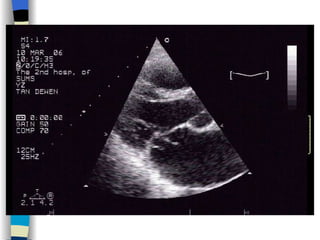

Echocardiography The most valuable technique for diagnosing MS, and determining its severity M-mode echo : Thickened, calcified leaflets open poorly, close slowly (EF slope ↓ ) The double peaks disappear Both leaflets move anteriorly during early diastole Two-dimensional echo: Fusion, thickening,  doming  of the valve leaflets, and poor leaflet separation in diastole;  mitral orifice area ↓

Echocardiography The mostvaluable technique for diagnosing MS, and determining its severity M-mode echo : Thickened, calcified leaflets open poorly, close slowly (EF slope ↓ ) The double peaks disappear Both leaflets move anteriorly during early diastole Two-dimensional echo: Fusion, thickening, doming of the valve leaflets, and poor leaflet separation in diastole; mitral orifice area ↓